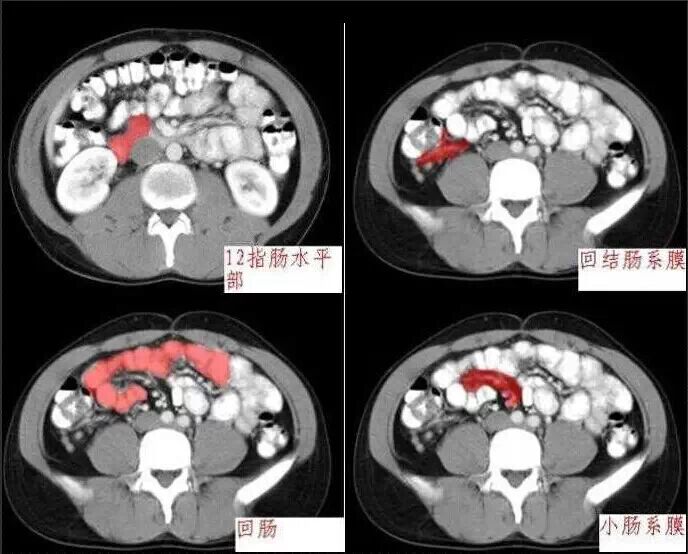

十分钟学会腹部CT解剖(多图)